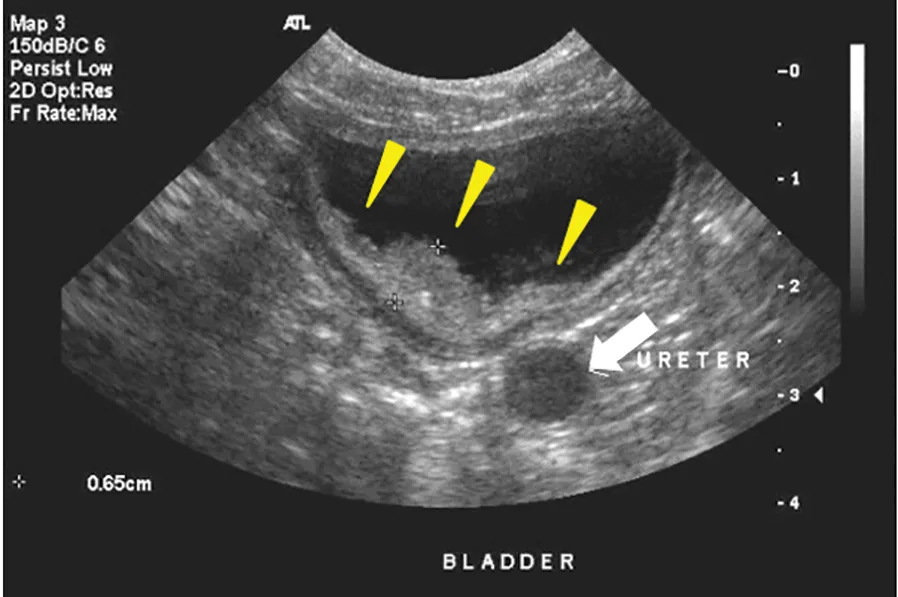

FIGURE 1

Classic sonographic findings of bladder TCC in a dog. A tumor mass (yellow arrowheads) arising from the deep muscle layers of the bladder wall extends into the bladder lumen, with chronic urinary obstruction resulting in development of hydroureter (white arrow). Photo courtesy of Louis-Philippe de Lorimier, DVM, DACVIM (Oncology)